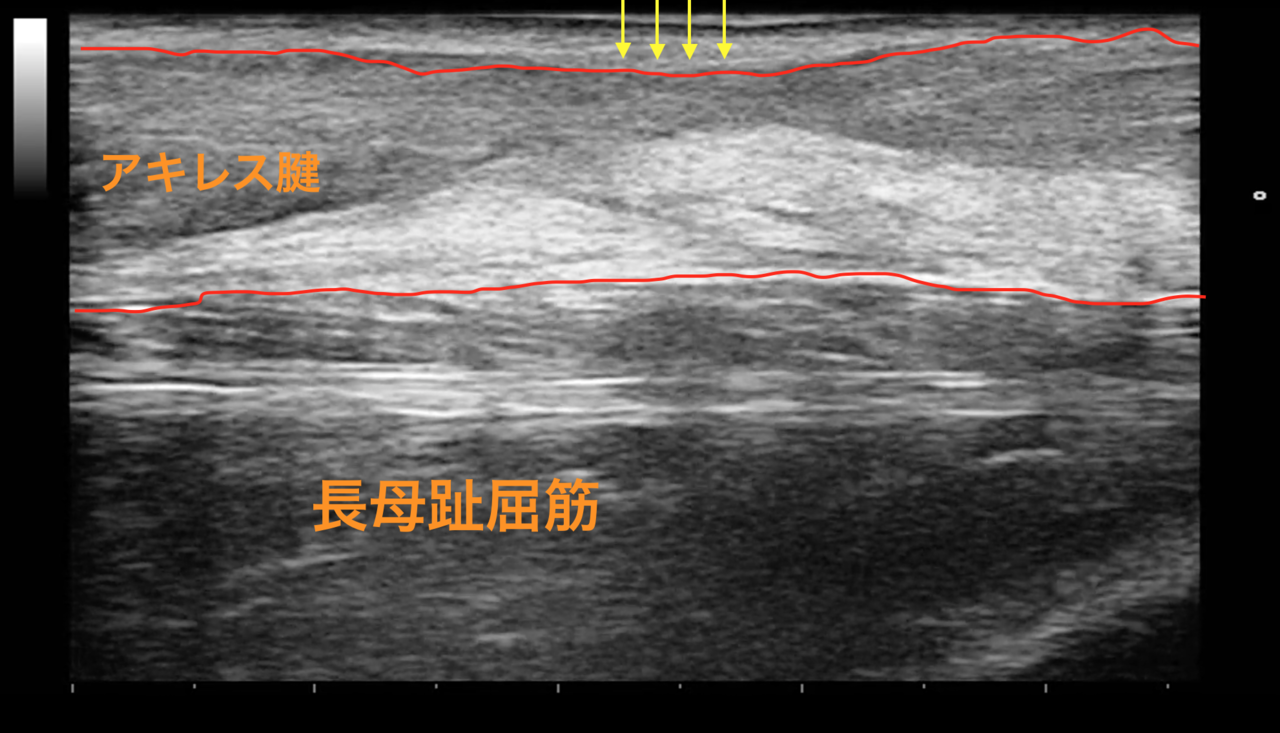

断裂部はやや細めだが再断裂の危険は少ない

断裂部はやや細め

触診とエコーで断裂部の状態を確認しました。

断裂部はやや細めですが、無理な力を加えなければよっぽど再断裂の危険は少ない状態と考えました。

危険な動作を避けながら荷重を少しずつかけ、積極的にリハビリトレーニングをしていただくことといたしました。

治療初期から適切なリハビリトレーニングをすることで、腱へ適切な機械的刺激が入り再生を促してくれます。

この方は3ヶ月半ほど経過していますが、腱の再生が少し遅いようでした。手遅れになるまへにお越しいただき本当によかったと思います。